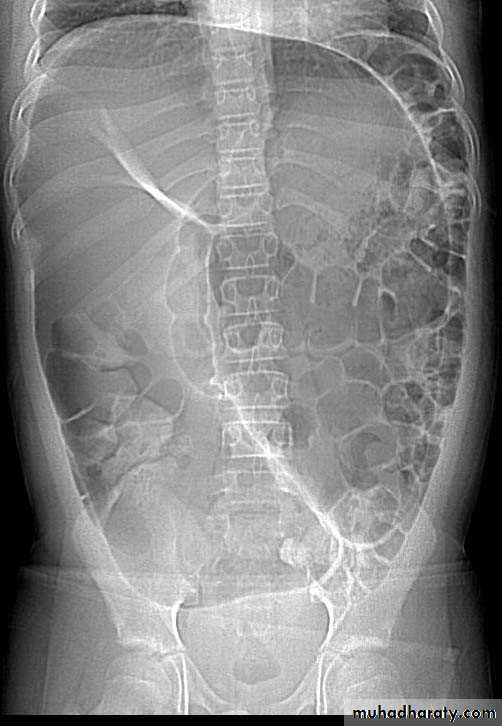

Small bowel obstruction

• The clinical presentation of small bowel obstruction (SBO) may include abdominal pain and vomiting, progressing to acute abdomen with abdominal distension and tenderness.

• Abdominal x-ray (AXR) is the primary investigation of choice in suspected small bowel obstruction.

• Signs of small bowel obstruction on AXR:

• Dilated small bowel loops, which have the following features• Central location.

• Numerous

• 2.5–5.0 cm diameter

• Small radius of curvature

• Valvulae conniventes, seen as white lines that are thin, numerous, close together and extend right across the bowel.

• Do not contain solid feces.

• Multiple fluid levels on the erect AXR

• ‘String of beads’ sign on the erect AXR due to small gas pockets trapped between Valvulae conniventes.

• Absent or little air in the large bowel.